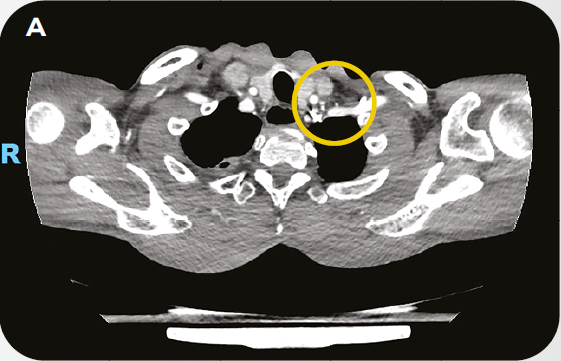

Caso Clínico: Tratamento de paciente com Câncer de Esôfago avançado com PPC>10 em 1L

O caso clínico compartilhado peo oncologista Dr. Rodrigo Guedes, constam detalhes sobre o tratamento de paciente com Câncer de Esôfago avançado com PPC>10 em primeira linha.